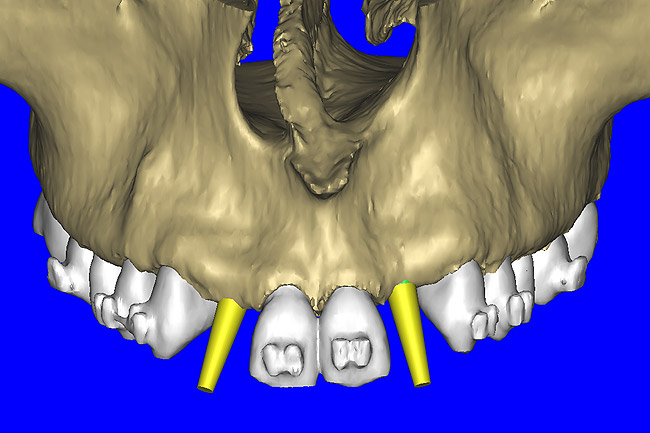

After the basic plan had been established, it was re-evaluated using interactive 3D images. The reconstructed 3D view of the maxilla clearly illustrated the extent of the bilateral facial concavities, and the root eminences of the adjacent and posterior teeth (Figure 7A). The placement of the virtual implants then was evaluated to ensure that the facial cortical plate was not perforated (Figure 7B). The implants were labeled individually as “7” and “10,” with the simulated yellow abutment projection indicating the facial-lingual inclination through the bone to the level above the incisal edge of adjacent teeth. The ability to gain a better understanding of these individual root forms can not be underestimated. The dental literature has suggested certain parameters for placing implants near teeth and implants next to other implants. However, there is little scientific 3D documentation to support these suggested rules.5-10 The use of an interactive treatment-planning software application permits closer scrutiny of previously difficult-to-visualize areas, and can now be used to redefine perceptions of spatial positioning of implants, especially when in close proximity to natural tooth roots, vital anatomy, and adjacent implants.27-29

Figure 7a  The 3D reconstruction showed (A) the facial concavities and root eminences, and allowed (B) for evaluation of virtual implant placement to ensure the facial cortical plate was not perforated.

Figure 7a

Figure 7b  The 3D reconstruction showed (A) the facial concavities and root eminences, and allowed (B) for evaluation of virtual implant placement to ensure the facial cortical plate was not perforated.

Figure 7b